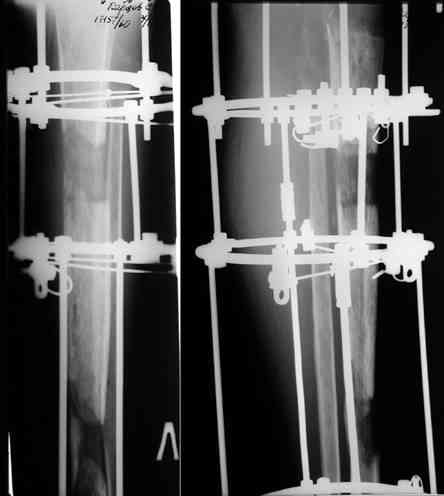

Прикрепляю пример замещения дефекта бедра 20 см, после резекции по поводу опухоли, эндопротеза Сиваша, вялотекущего остеомиелита со свищами в течении 3 лет. Получилось хорошо и всего за 6 месяцев в аппарате. Колена не было. У Вас случай сложнее. Это было в 1998г. Я работал в ЦИТО и у меня было 4 больных, я занимался им с утра до ночи. Сейчас 60 больных и операций в нашем отделении 25-30 в неделю.Если могу чем помочь - нет проблем.